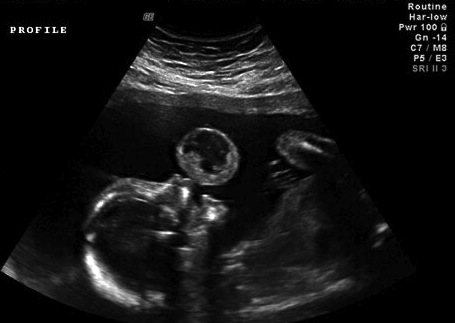

The ultrasound image shows the nasopharyngeal teratoma as a "bubble" protruding in front of the lip of the fetus.

The tumor was resected at the base using a 600 micrometer contact YAG laser fiber on continuous mode with 10 W of energy. A minimal amount of bleeding from the base of the tumor was controlled with a noncontact YAG laser fiber. The tumor fell inside the amniotic cavity, where it was left. The procedure lasted 68 minutes. There were no maternal or fetal complications.Further details (fulltext) at the American Journal of Obstetrics & Gynecology, via the BBC.